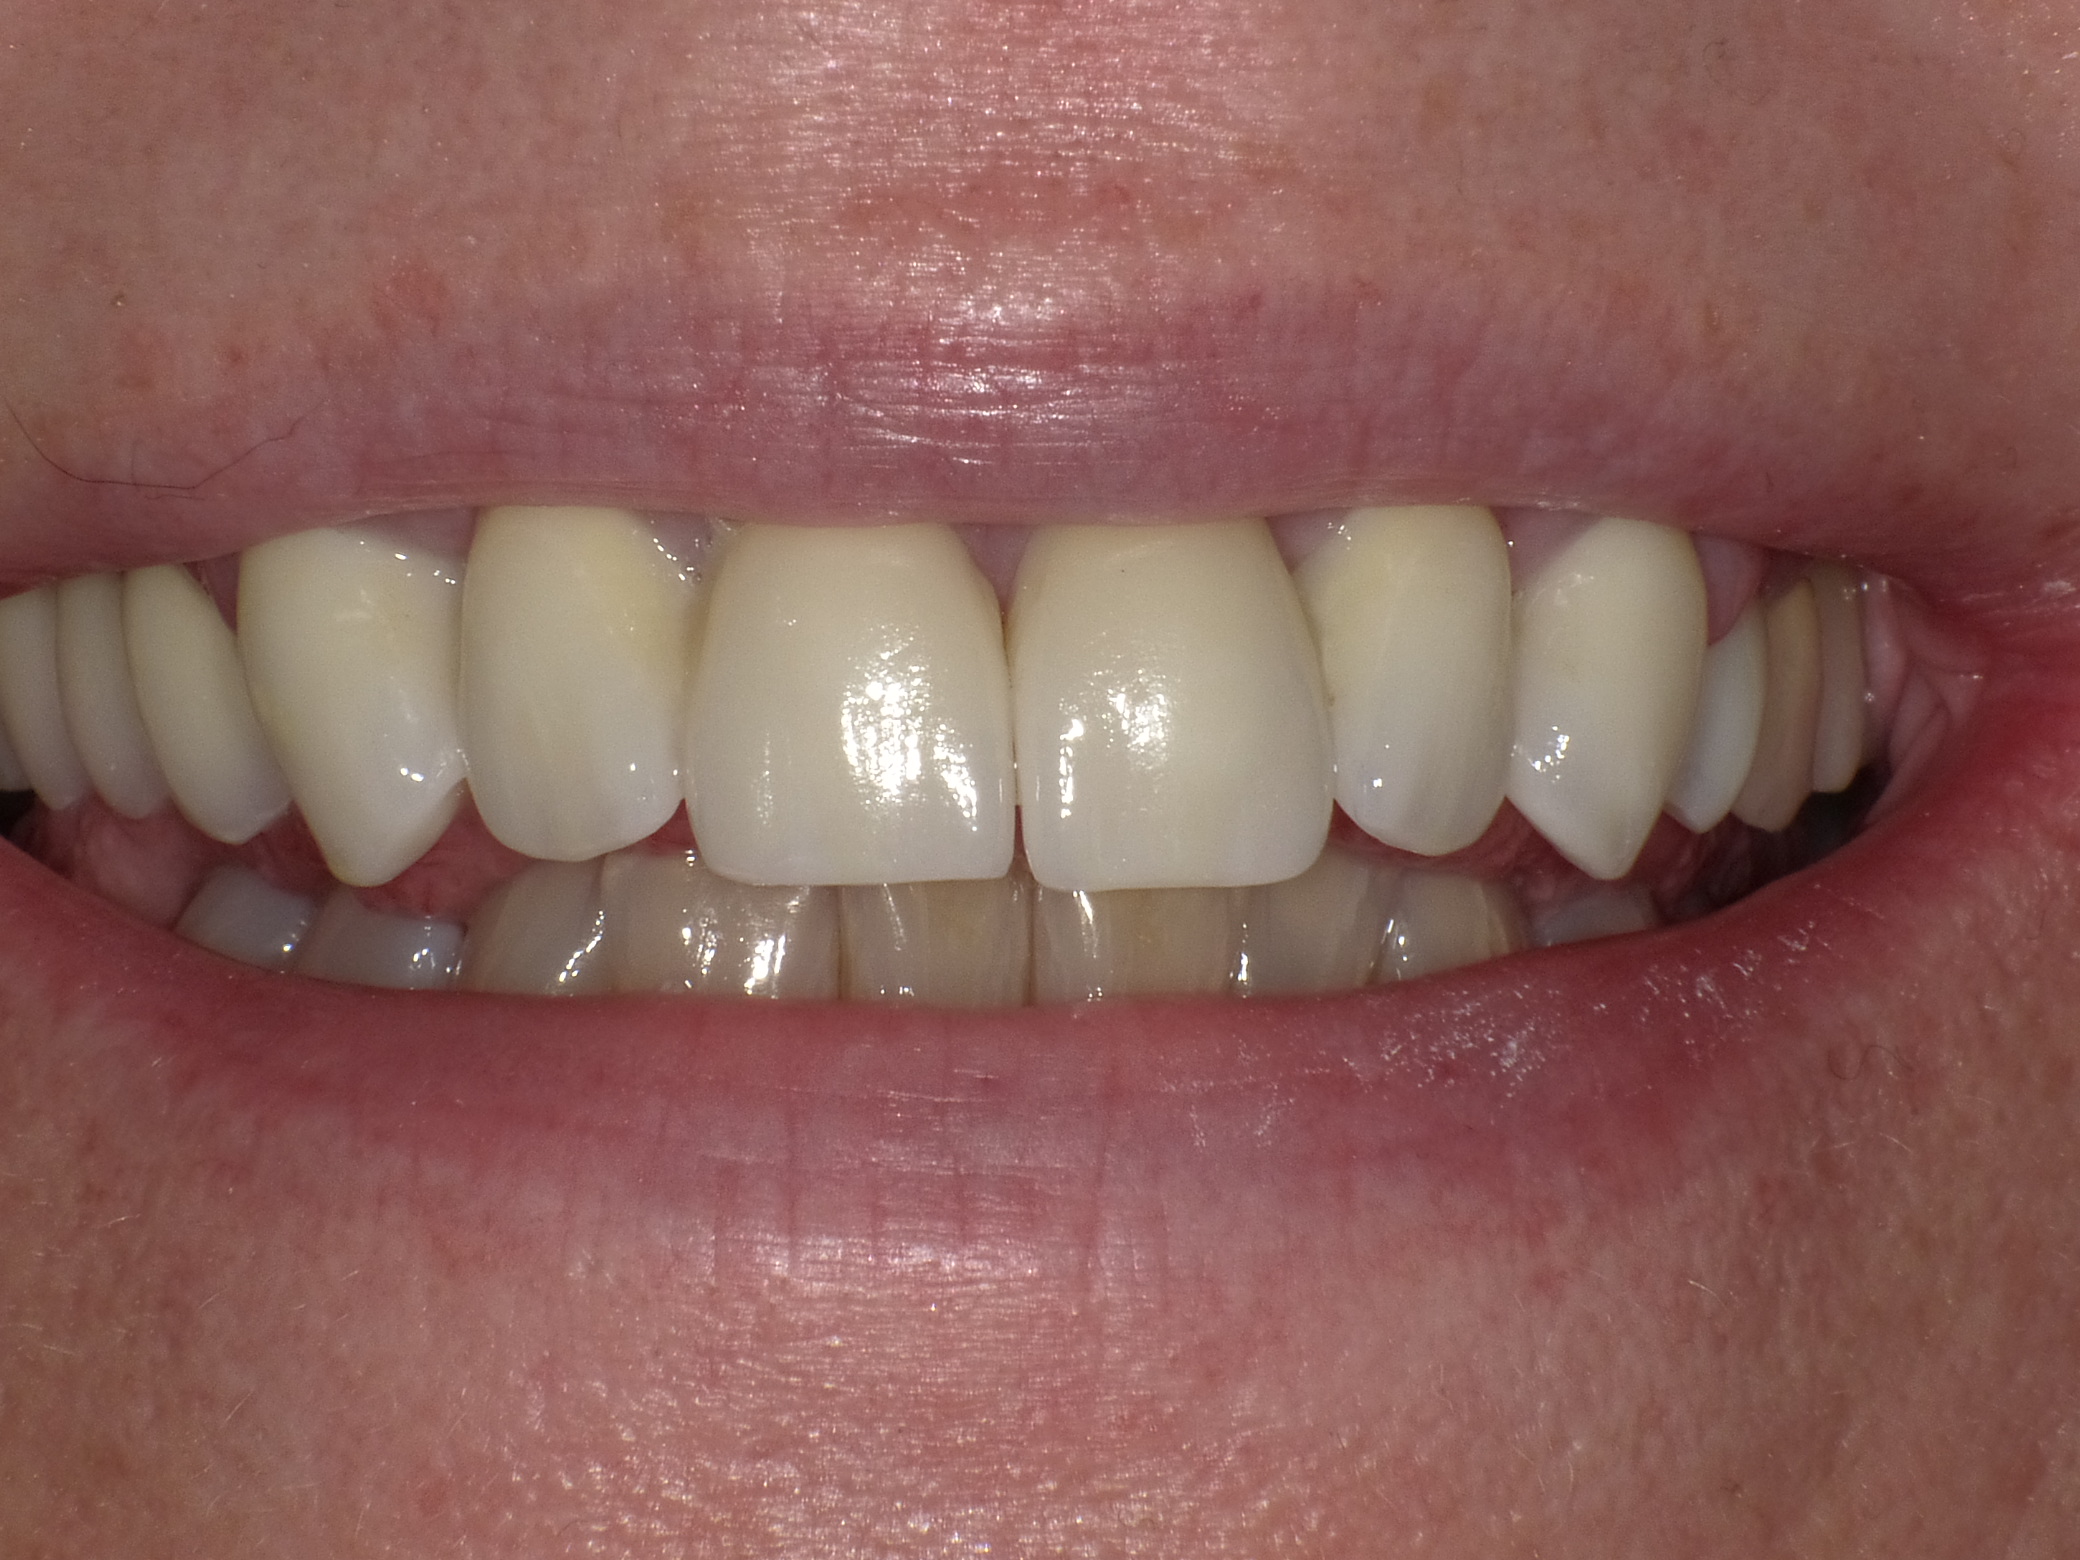

Patientin mit dem Wunsch nach ästhetischer Optimierung der Gesamtsituation

Vorher: Patientin mit dem Wunsch nach ästhetischer Optimierung der Gesamtsituation

Ergebnis nach nur 2 Langzeit-Behandlungsterminen mit vollkeramischen Veneers und Kronen

Nachher: Ergebnis nach nur 2 Langzeit-Behandlungsterminen mit vollkeramischen Veneers und Kronen